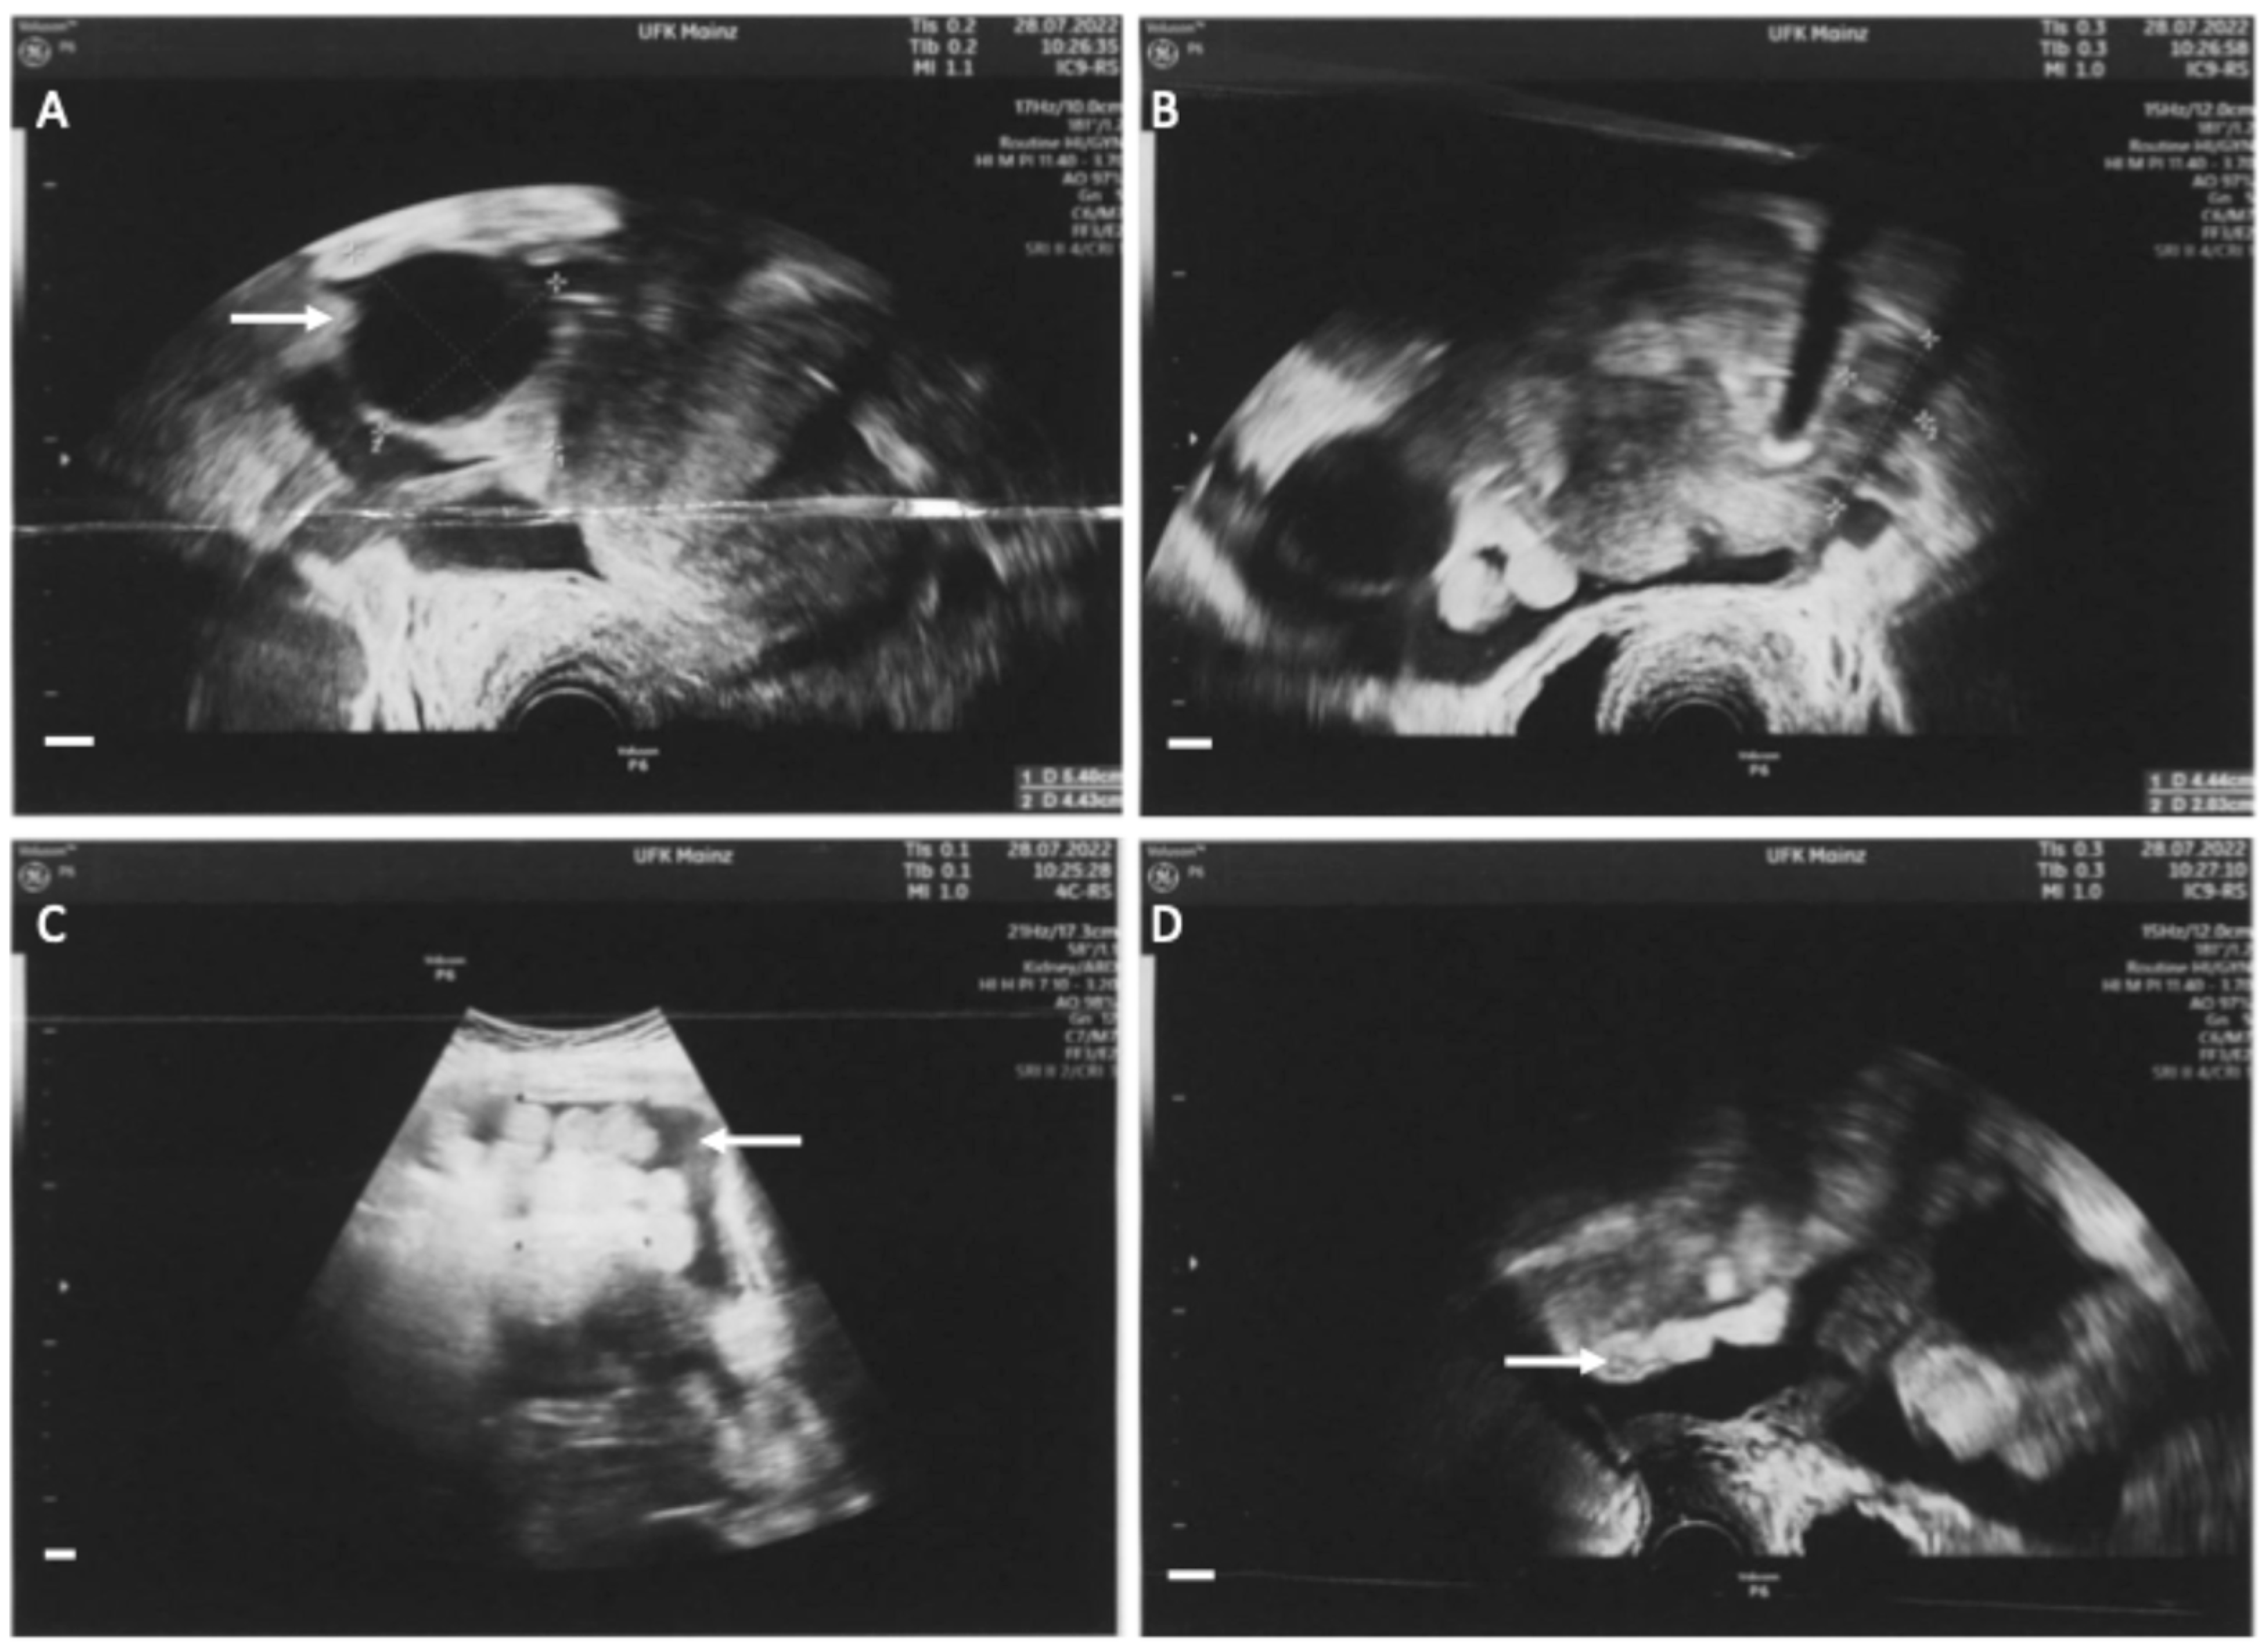

Figure 1.

Sonographic assessment at first presentation in our clinic. (A): Enlarged right ovary with an unilocular tumor of 5.4 × 4.4 cm with low echogenicity and a papillary structure (white arrow). (B): Left ovary without pathologic findings. (C): Ascites (white arrow). (D): Peritoneal carcinosis (white arrow). The combination of these findings (ovarian tumor, ascites and peritoneal carcinosis) are potentially indicative of ovarian cancer. All white bars in the bottom left-hand corner indicate 1 cm.